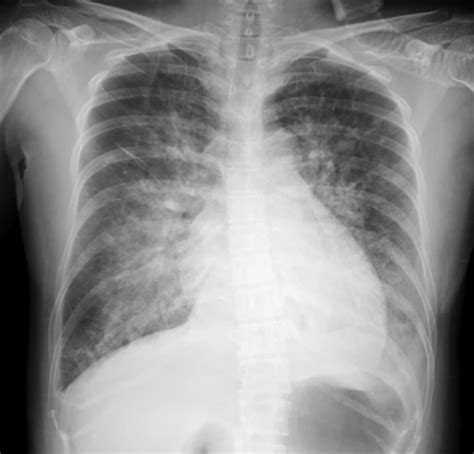

So, how do doctors figure out if you have pulmonary interstitial edema ? They usually start with a physical exam, listening to your lungs with a stethoscope. They might also order some tests, like a chest X-ray, which can show fluid in the lungs. A CT scan can provide more detailed images. Blood tests can help identify underlying conditions like heart or kidney problems. An echocardiogram can assess your heart function. These tests help give the doctor a clear picture of what’s going on. Here’s a quick rundown:

• Chest X-Ray: This imaging test can reveal fluid accumulation in the lungs and identify other potential causes of respiratory distress.